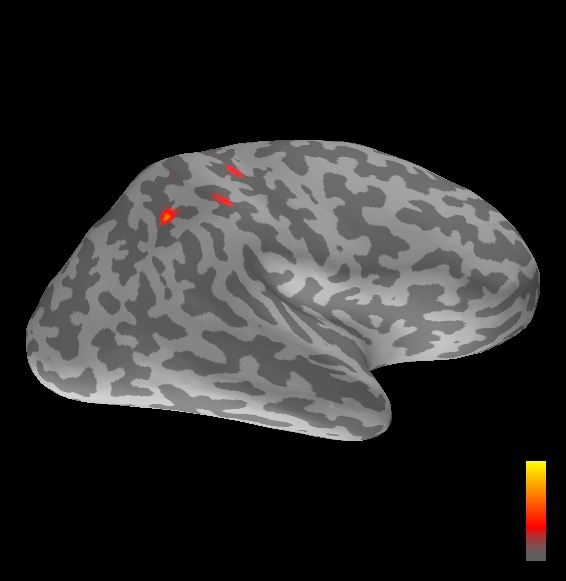

5.2 Results

We applied the ASMC sampler to MEG topographies taken from the above recordings by selecting specific time points according to the previous analysis; the parameter values in the algorithm were the same as those used for the analysis of synthetic data, with the only exception of the noise standard deviation , here estimated from the pre–stimulus interval. In order to validate the results of the ASMC, we also computed source estimates using three other methods: a PF, that approximates the posterior distribution for the current dipoles conditioned on the data up to the selected time point; dSPM, which is based on a distributed source model with an –prior, and consists in normalizing the Tikhonov regularized solution by the noise standard deviation; and sLORETA, which is similar to dSPM but is claimed to have a smaller localization bias. Figure 4 shows the results at , and ms after the stimulus onset. The results are visualized on a computer representation of the brain obtained by “inflating” the cortical surface: gray levels contain the anatomical information, light gray representing gyri and dark gray representing sulci; the activity estimate is coded in color scale, increasing from red to yellow. Importantly, this visualization allows activity in the sulci to be clearly visible; on the other hand, since neighbouring volumes may be moved apart by the inflation process, distinct activity regions are often due to underlying volumetric masses that are very close to each other.

Before describing the results, let us comment on the qualitative difference between the images produced by the ASMC sampler and the PF, on the one hand, and those produced by dSPM and sLORETA, on the other. First of all, we point out that all the quantities shown in the images of Fig. 4 are somehow related to the probability of activation at specific locations. Indeed, for both the ASMC and the PF we plot the approximation of the intensity measure (3.8); for any single grid point, this value can be interpreted as the probability of a dipole being at that location, while it integrates, over a given volume , to the mean number of dipoles within . As for dSPM, the represented quantity is a statistical value that is –distributed under the null–hypothesis of zero activity; as a direct consequence, it also yields a probability of activation, which is however not constrained to be dipolar. Similar considerations apply to sLORETA, although with a different statistical distribution. Importantly, the representation of the results is clearly affected by the setting of the visualization threshold. Owing to the explained differences between the methods, it seems reasonable to use a different value for each method. At the same time, since the plotted quantity is a probability of activation, it seems right to use the same thresholding for different time points. In this connection, the thresholds in Fig. 4 have been chosen by hand following the guidelines just outlined.

Using the same thresholding and parameters at different time points makes the four methods respond differently to the diverse intensities of the different sources. Whenever a stronger source is active, both sLORETA and dSPM will tend to produce widespread estimates, while weaker sources will be represented as small active areas. The behaviour of the ASMC and of the PF is the opposite: a stronger signal will lead to a precise localization of a dipolar source, and then to a focal marginal distribution for the location; a weaker signal will translate to higher uncertainty on the source position, and therefore a more widespread posterior map.

At ms, the ASMC localizes two sources, one in the right hemisphere and a weaker one in the left hemisphere; these sources appear to be compatible, for timing and location, with the Posterior Parietal Contra and Parietal Opercular Ipsi described in Mauguiere et al. (1997). The PF finds the very same source in the right hemisphere, but it estimates no dipoles in the left one. Such discrepancy between these two methods, which are based on the same source model, is possibly due to two facts: first, thanks to its iterative nature, the ASMC is likely to explore the state space more thoroughly and is therefore more suited to identify weak sources; second, the log–uniform prior on the strength of the dipole moment in the ASMC has a wider range than the corresponding Gaussian prior in the PF. Slightly different results are provided here by dSPM and sLORETA. The activity estimate computed by dSPM seems very similar to that of ms, having the same spatial distribution with a weaker intensity. The estimate of sLORETA in the right hemisphere includes that of the ASMC and of the PF. Neither dSPM nor sLORETA find significant activity in the left hemisphere.